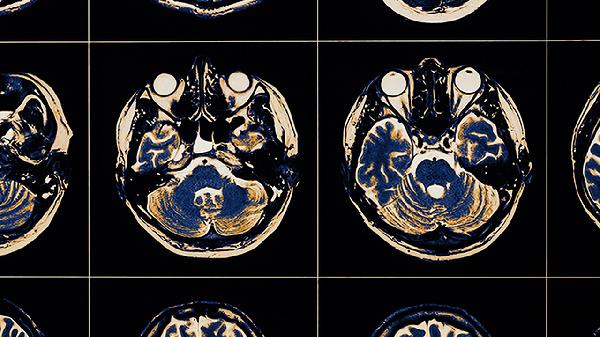

脑血栓如何调理 脑血栓的几个调理方法介绍